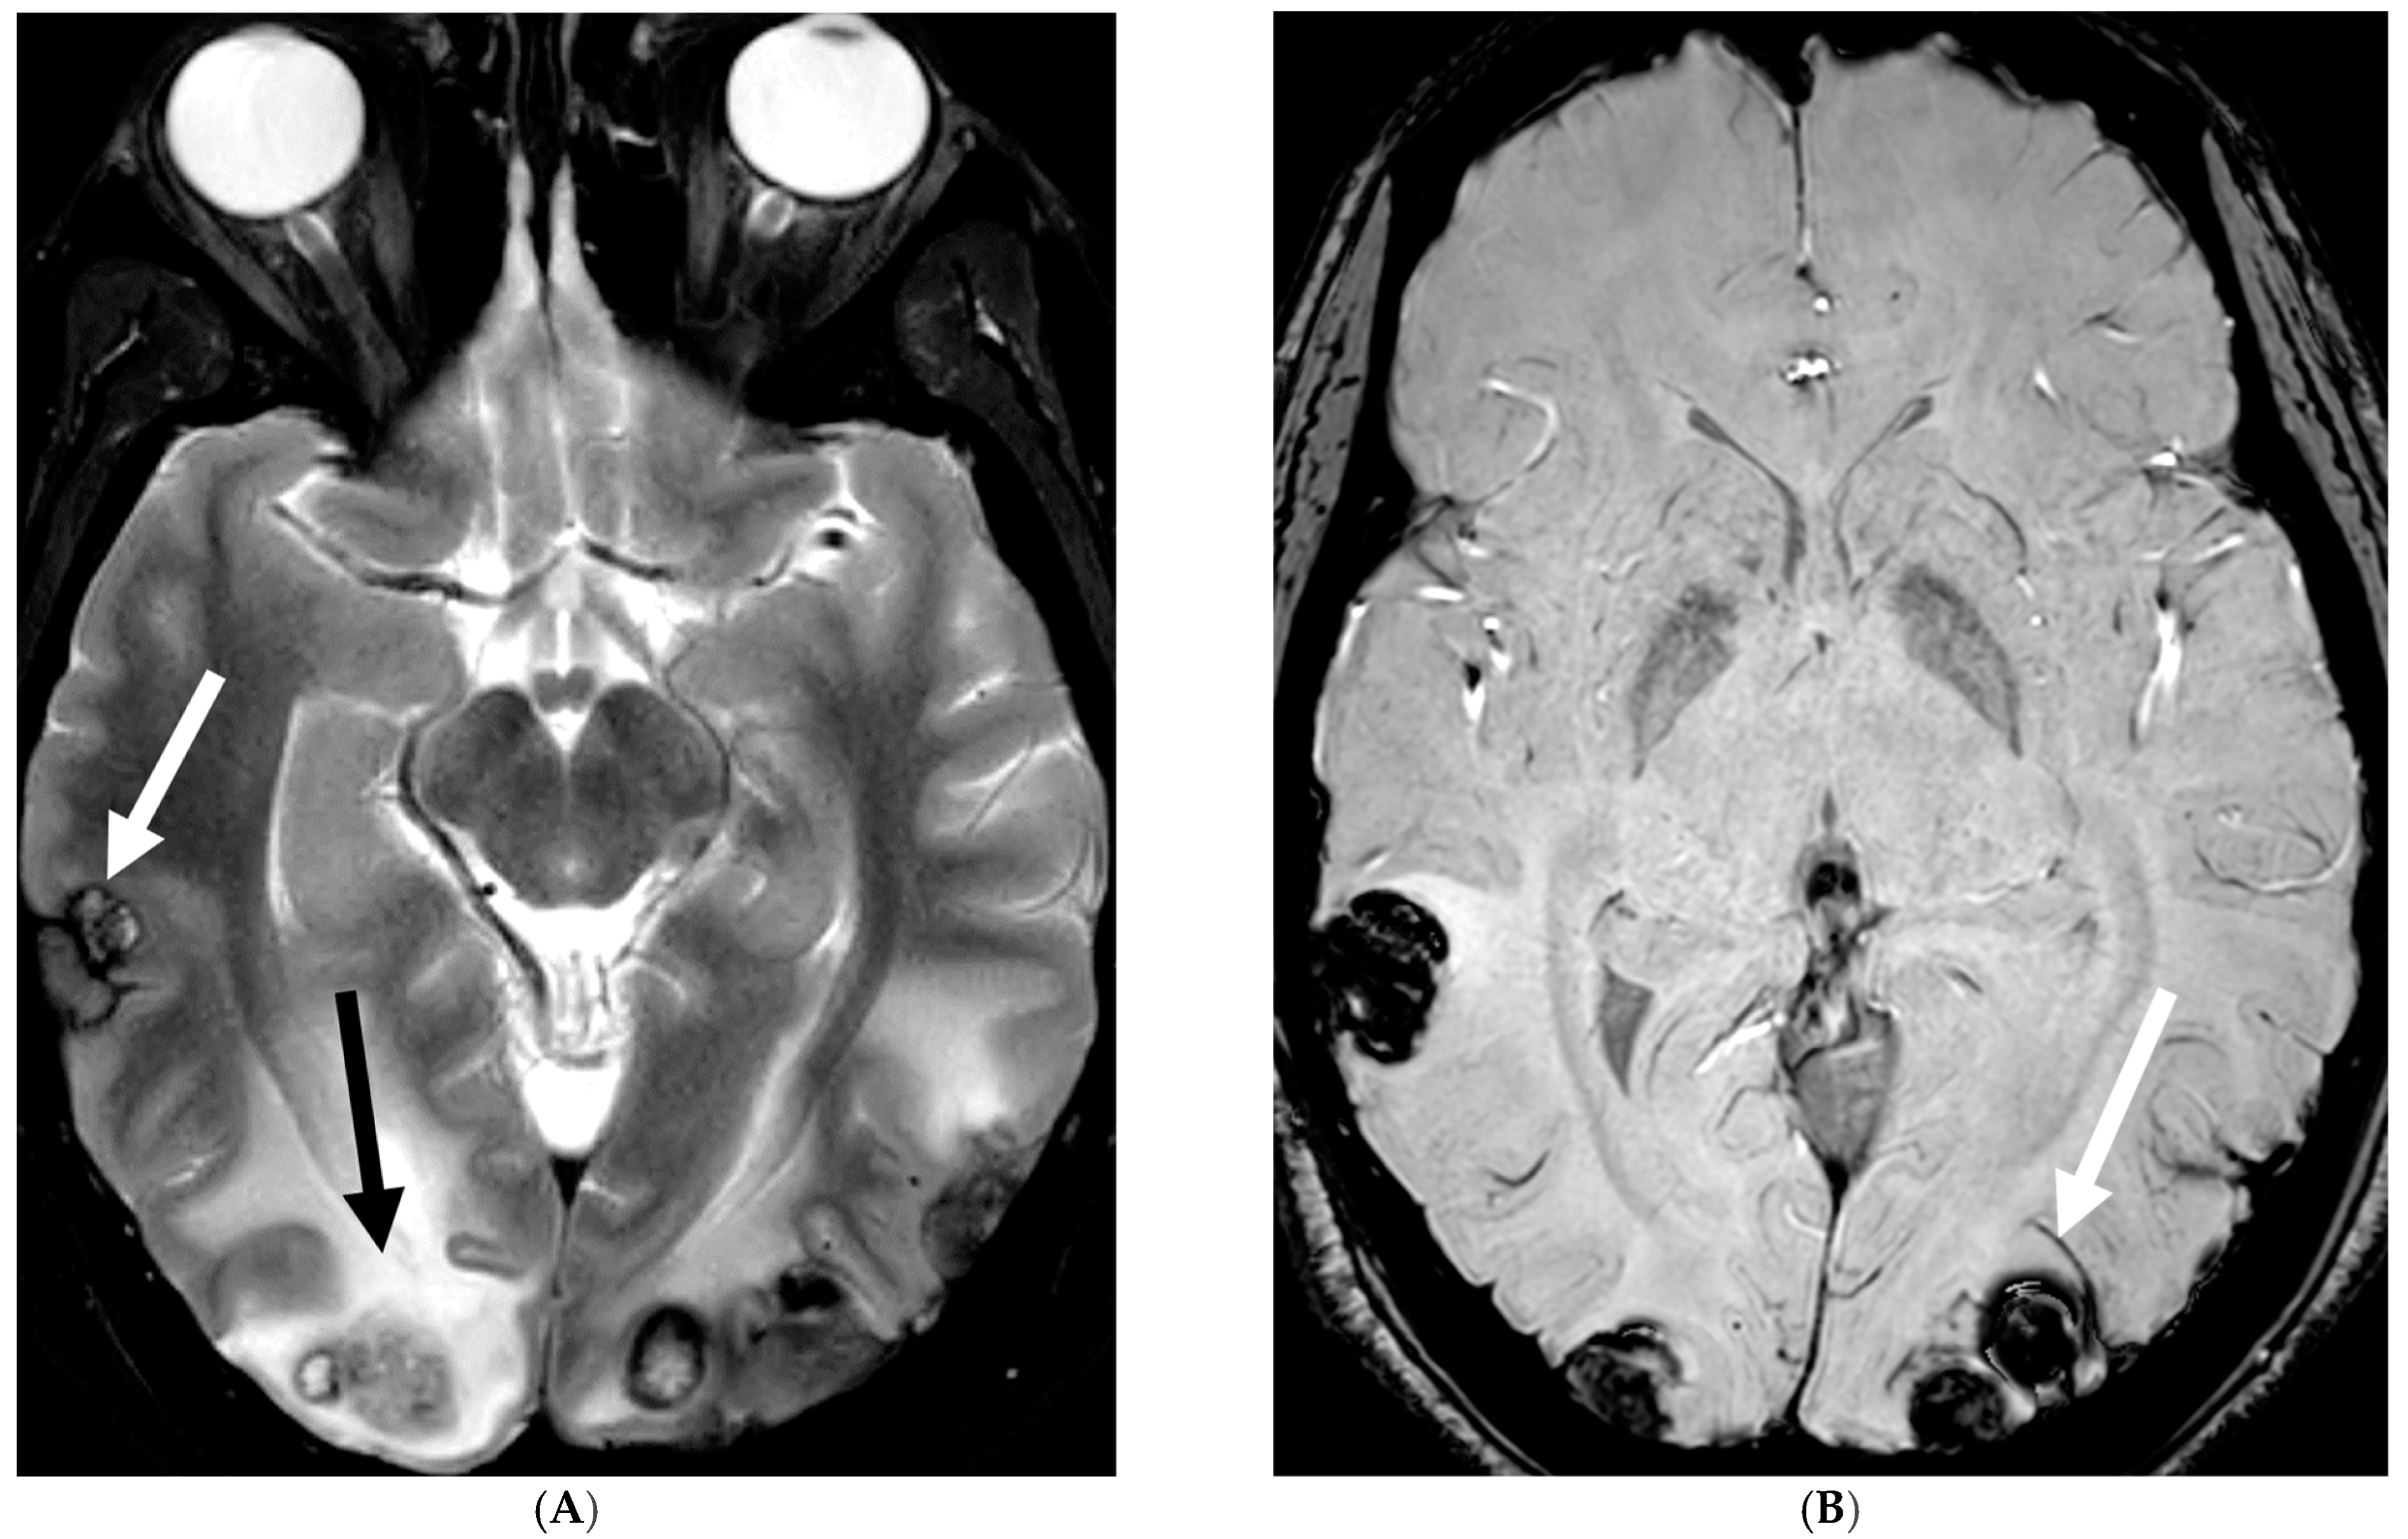

Figure 10.

Axial T2 (A), sagittal T1 post contrast (B), Sagittal T2 (C,E) and sagittal T1 post contrast (D,F): 20-month-old boy with 2 months of losing developmental milestones and 1 month of emesis, fatigue and dehydration. Ventriculomegaly with transependymal fluid is noted (black arrows). There is posterior fossa leptomeningeal nodular enhancement extending into the upper cervical spine (curved white arrows). Extensive nodular enhancement along spinal cord (dashed white arrows) with cord edema demonstrated in the entire cord (white arrows).

Figure 11.

3 weeks follow up: Post contrast sag T1 (A) and axial FLAIR (B), Axial T2 (C), sagittal T2 (D), Post contrast sagittal T1 (E) and PET/CT (F): Leptomeningeal nodular enhancement along posterior fossa, suprasellar and spinal cord (curved arrows) has significantly increased. There is also new/increased signal abnormality in the brain stem and cord (white arrows). Hypermetabolic spine disease is demonstrated on PET/CT. No osseous involvement is identified on the PET scan. Pathology: Diffuse CNS ALK (Anaplastic Lymphoma Kinase)-Positive Histiocytosis. Bone marrow biopsies, US abdomen and skeletal survey negative for extracranial/extraspinal disseminated disease.